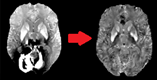

Figure 1 : QSM obtenu sans pré-traitement (gauche) et avec (droite).

La figure 1 montre un exemple du QSM calculé dans le Cloud en utilisant le pipeline implémenté en CWL qui est exécuté dans un environnement virtuel contenant tous les modules Python nécessaires.